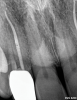

Other common risks associated with post placement include the occurrence of root fracture, perforation, and apical leakage as well as the development of caries (Figure 1 through Figure 3).9 How the post space is prepared significantly affects the ability of the root canal filling material to create a seal.11 Apical leakage increases in correlation with the amount of gutta percha removed from an endodontically treated tooth, increasing the risk of reinfection.11 The risks of fracture and perforation must also be seriously considered. After the performance of endodontic treatment alone, furcation-side dentin thickness in the distal roots of mandibular molars has been shown to be less than 1 mm in more than 80% of teeth.12 After preparation of the post space, the remaining dentin thickness in the buccal roots of premolars has been shown to be often less than 1 mm.13 The remaining thickness of the root dentin after endodontic and post placement procedures is the factor most highly correlated with future resistance against root fractures.13 These anatomic studies underscore the need for judicious preparation, and the risks of post placement underscore the need for careful case selection.

(2.) A radiograph of a root fracture associated with a threaded post, cone-beam computed tomography views of a perforation associated with a post, and a radiograph demonstrating evidence of apical leakage associated with posts, respectively.

Figure 2